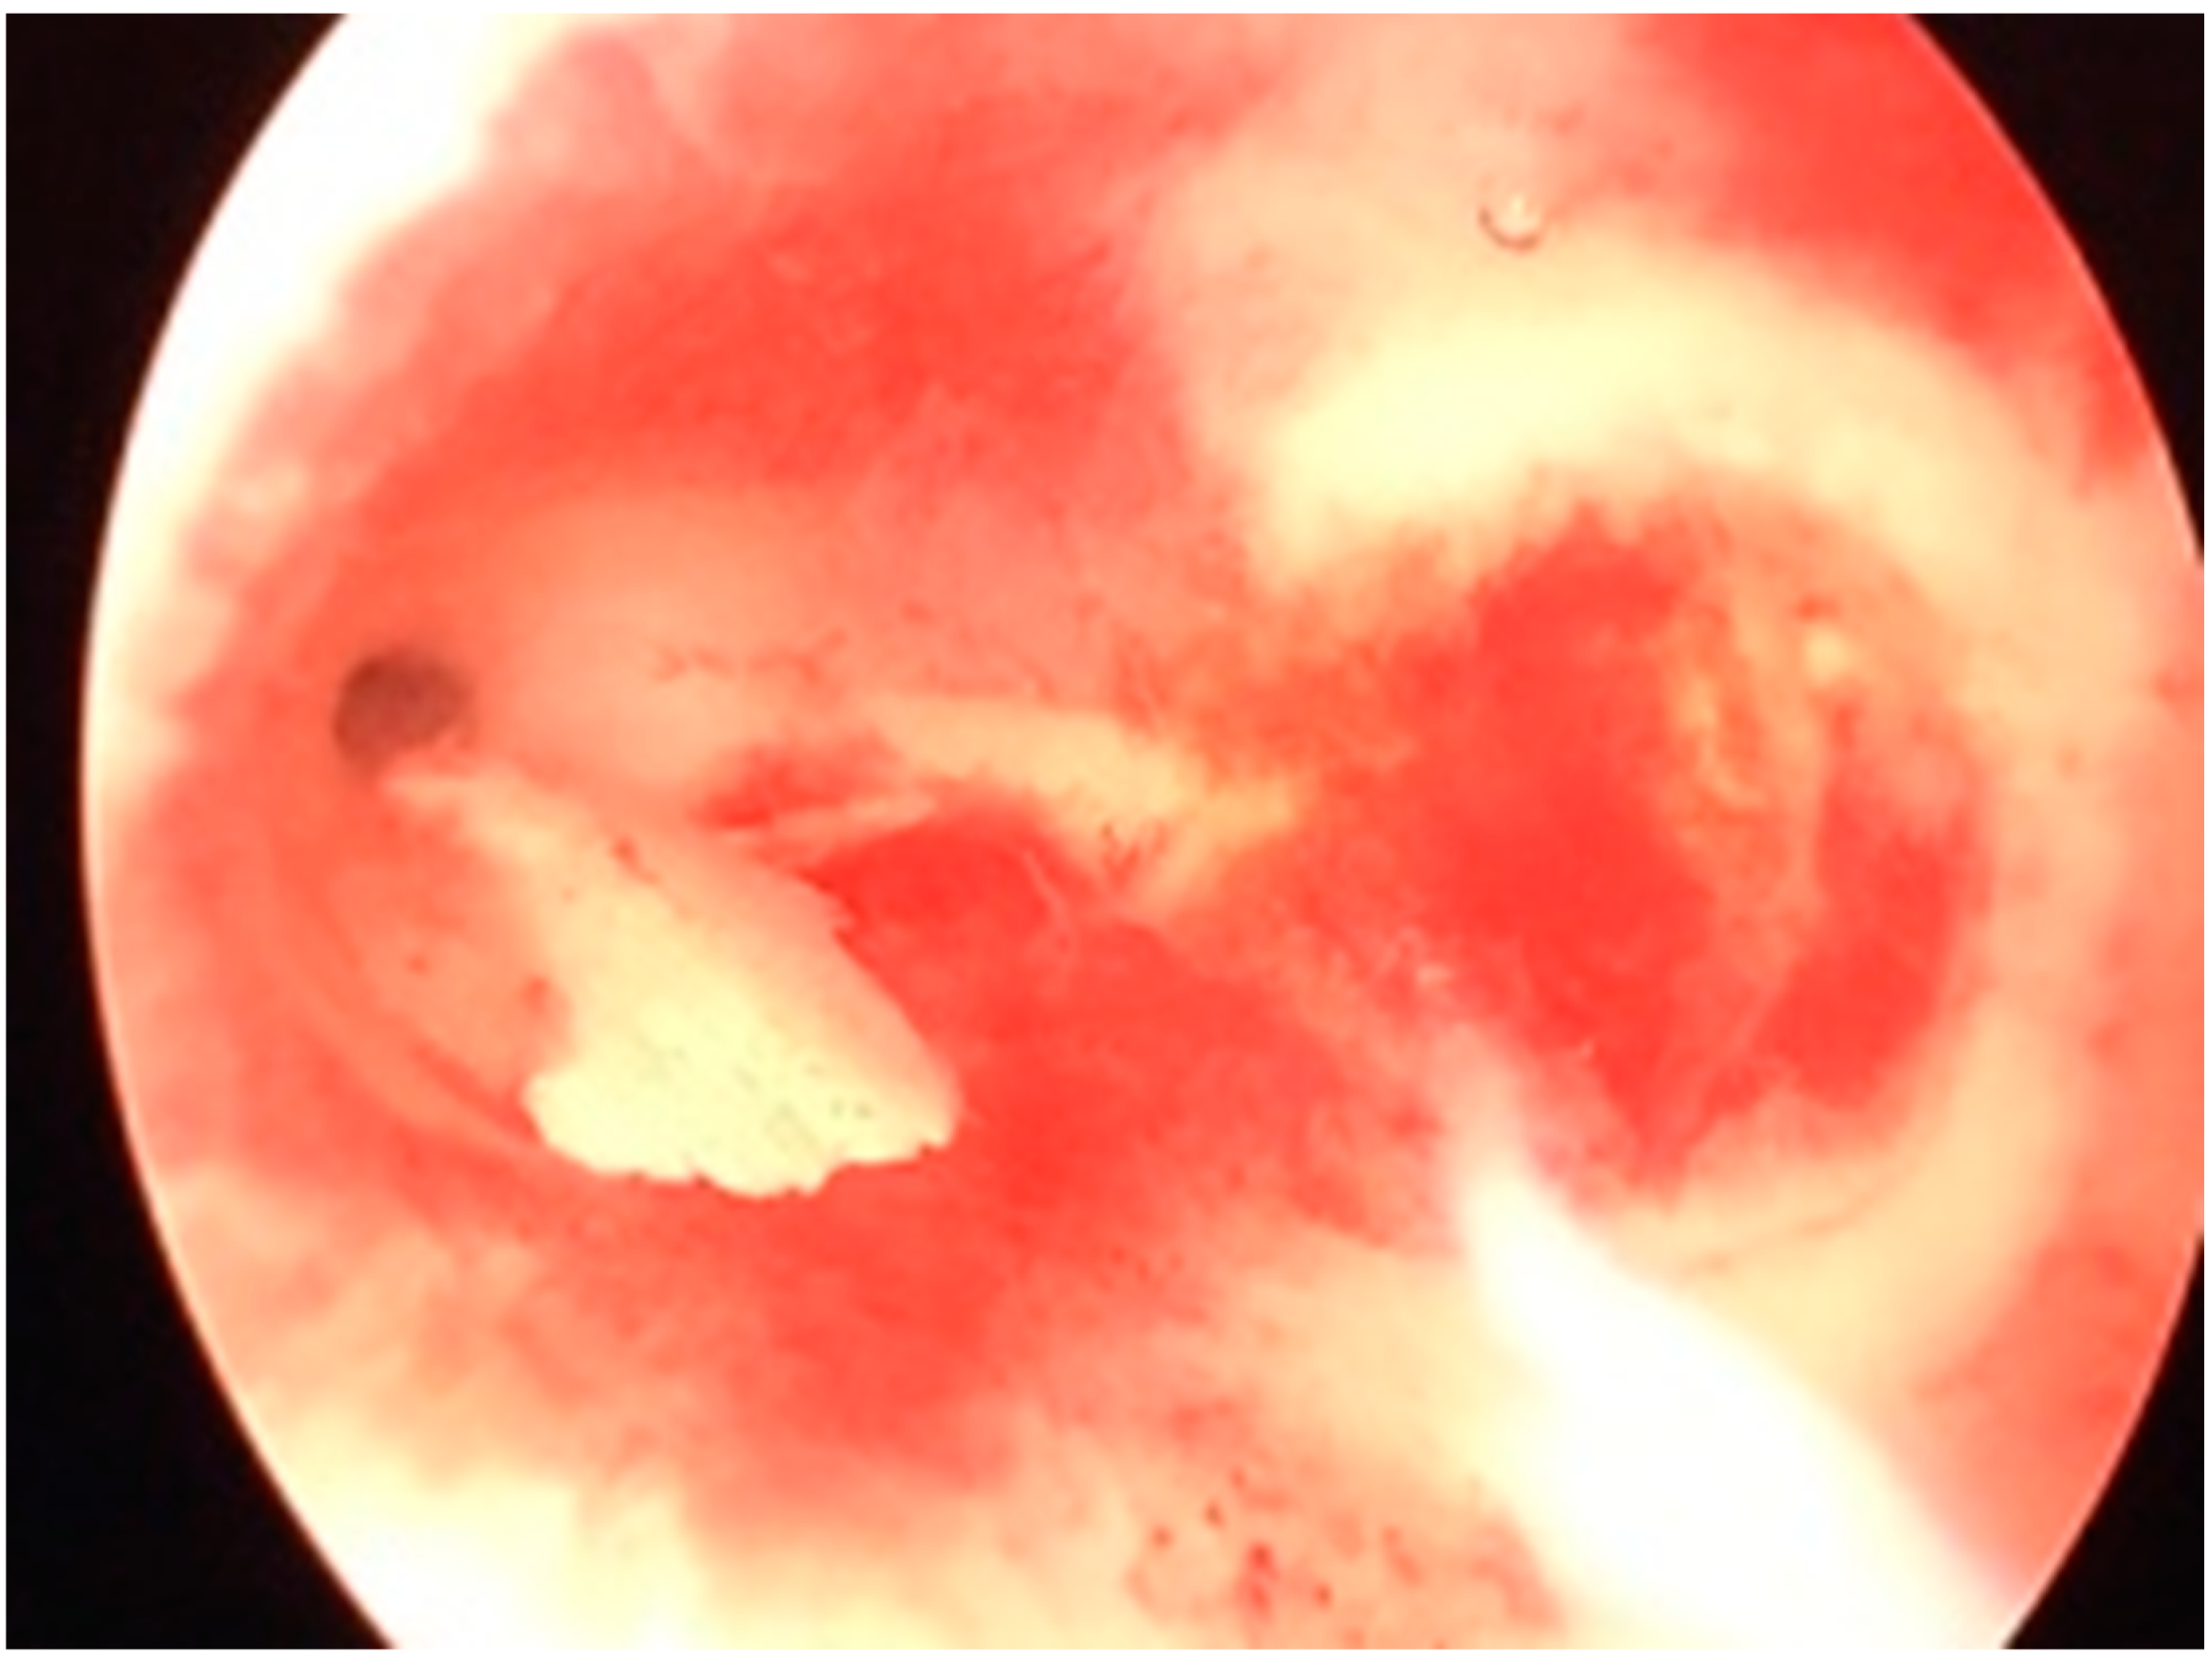

Case Report